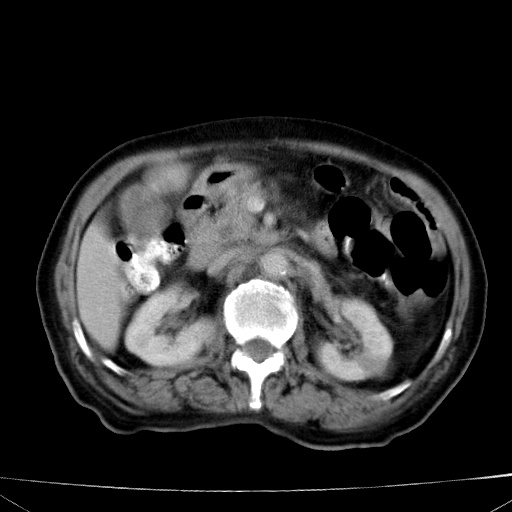

网站人气太旺!昨天的帖子就沉到海底,只好再发贴!ct18338:女 78岁,肝胆病变,已增强,再会诊!原帖链接:http://www.radida.com/bbs/forum.php?mod=viewthread&tid=50032

1)考虑胆囊癌侵犯肝脏并肝门区、腹膜后及右侧膈角后淋巴结转移。2)肝左叶近肝顶部囊肿。3)肝左叶肝内胆管结石。4)左肾近下极囊肿。